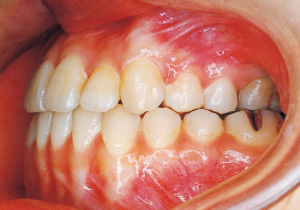

2 After Phase 2 Treatment 5-9-’92

Aware that treatment would be challenging, we proceeded with the first phase of treatment based on the current functional status and anticipated developmental implications (7). During the mixed dentition phase, the body responds readily to treatment, allowing for relatively rapid tooth movement and changes in jaw position (8,9). Subsequently, once freed from mechanical stimulation, growth continues according to inherent predispositions, often appearing to disregard occlusal functional efficiency (10,11). These changes are clearly observable on cephalometric radiographs (12). After confirming the extent and direction of growth, we decided to incorporate surgical intervention into the treatment plan and wait until the age when growth begin to decline.

10 6-25-’84 During observation 12 years and 11 months old

11 9-28-’85 During observation 14 years and 2 months old

Afterwards, follow-up was conducted, but based on the growth pattern, surgical intervention was determined necessary, and the patient entered a period of regular observation.

Regular Observation: 8 years from 10 years 11 months to 18 years 11 months